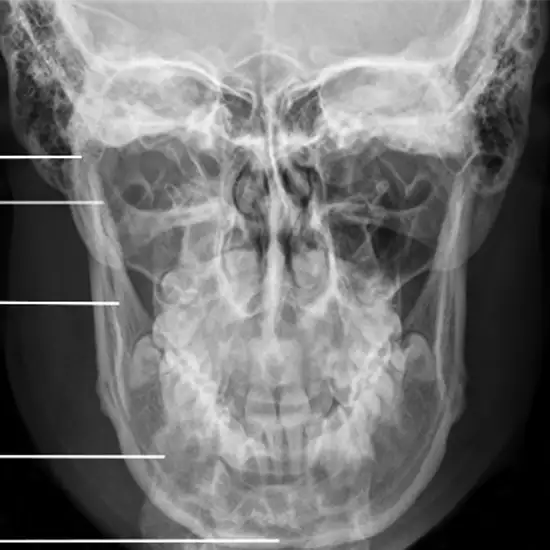

What is an X-ray Mandible Pa Right Lateral Oblique Test?

An X-ray of the mandible, also called the jaw, can be used to look at the structures of the jaw bone, the TM joint, and the muscles and other soft tissues in the area.